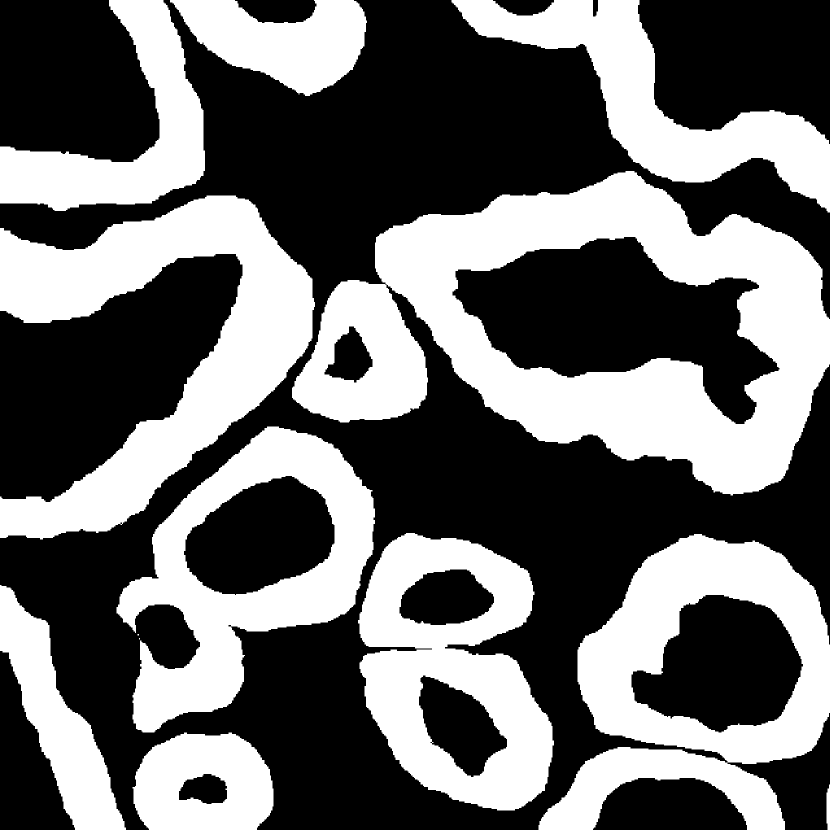

Fig. 3 shows two image examples, their ground-truth masks, and the final segmentations generated by competing models. Comparing with U-Net, Res-Seg based models generally have fewer false positives. Comparing with Res-Seg-Net, Res-Seg-Net and Res-Seg-Net both generate cleaner outputs, which can serve as an evidence that hierarchical refinings are effective in improving segmentations in both accuracy and robustness. These effects can be clearly seen within the areas highlighted with green boxes.